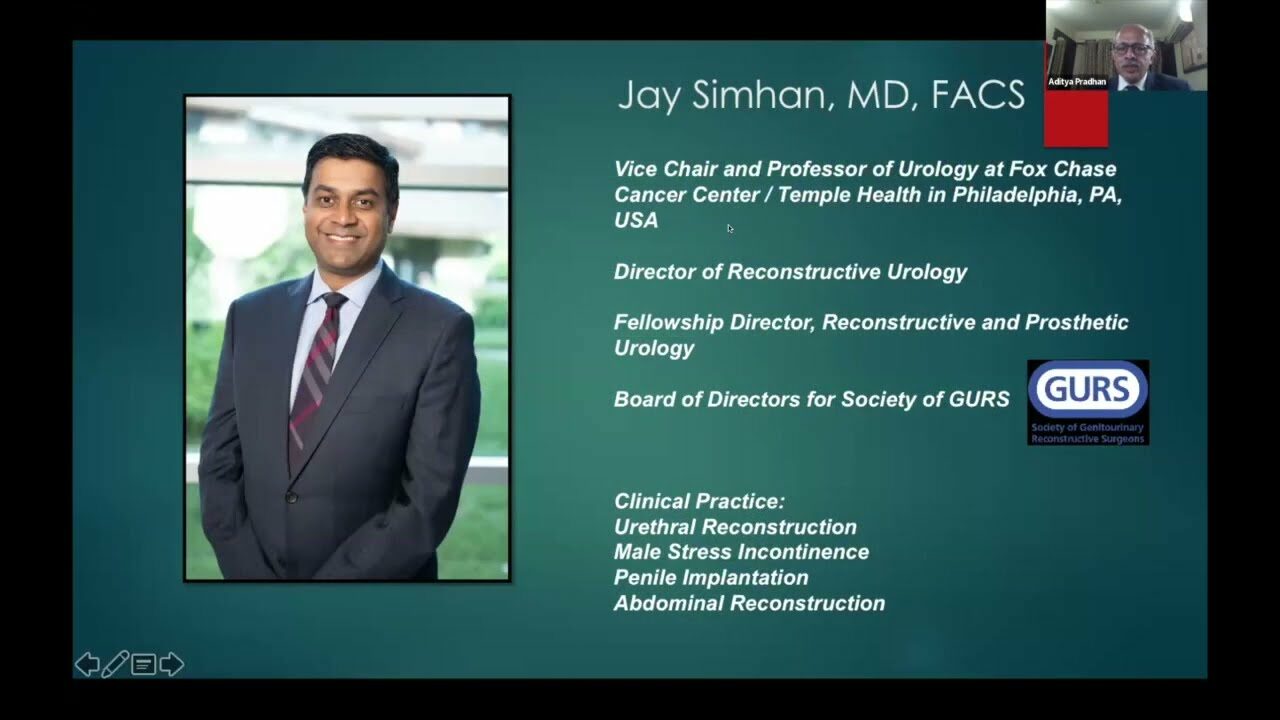

An Algorithmic Approach to Manage AUS Failure- Dr. Jay Simhan

Masterclass, Robotics, Surgeon, Urology ';